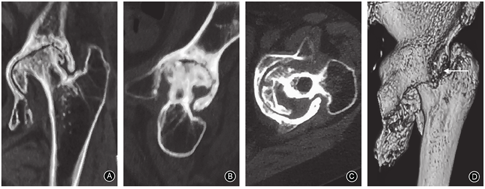

影像学检查:骨盆正位X线片示双侧髋臼内陷,髋关节病变继发双侧股骨头坏死,伴左侧股骨颈GardenⅡ型骨折(图1)。CT扫描示髋臼壁硬化,髋臼口增生明显,股骨颈皮质不连续(图2)。髋关节内陷程度:Sotelo-Garza和Charnley分型Ⅱ型。